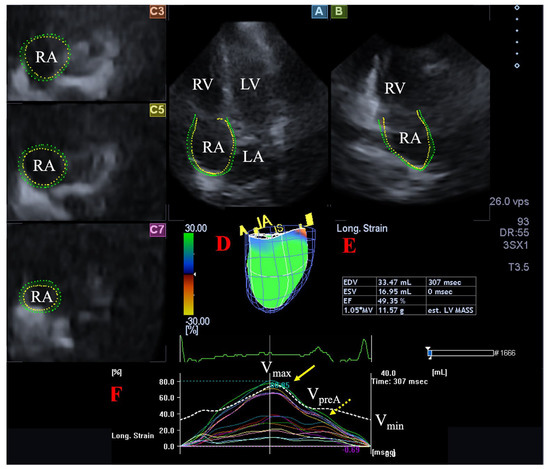

2.4. Quantification of 3DSTE-Derived RA Volumes and Strains

- Maximum RA volume, measured at end-systole, just before tricuspid valve opening (Vmax).

- RA volume before atrial contraction, measured at early-diastole at the time of P wave on ECG (VpreA).

- Minimum RA volume measured at end-diastole, just before tricuspid valve closure (Vmin).

- Radial strain (RS) representing the thickening/thinning of a certain RA segment.

- Longitudinal strain (LS) representing the lengthening/shortening of a certain RA segment.

- Circumferential strain (CS) representing the widening/narrowing of a certain RA segment.